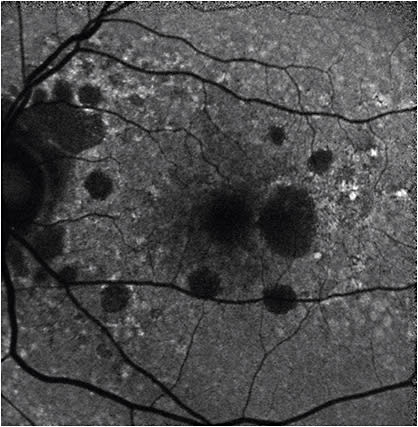

Fundus autofluorescence (FAF)

FAF relies on the visualization of lipofuscin pigment in the RPE, which increases with aging and various retinal diseases. It allows for identification of high-risk characteristics such as focal hyperpigmentation, which presents as increased signal intensity or hyperfluorescence. It also highlights areas of hypopigmentation, with decreased signal intensity or hypofluorescence correlating with RPE loss (Figure 3, page 19). By allowing direct visualization of GA, FAF is most beneficial for the initial assessment and monitoring of patients with GA — specifically perilesional hyperfluorescence, which often precedes further retinal atrophy.12,13